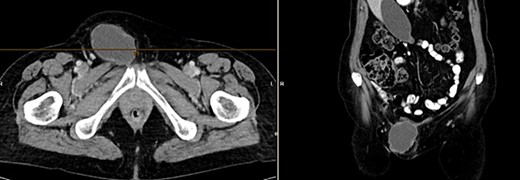

Further clarification was sought through a computed tomography (CT) scan of the entire abdomen (Fig. 1). The CT from 25 February 2022 showed an oval, encapsulated structure in the right groin area, most likely interpreted as a soft tissue hematoma. No active bleeding was observed. An enlarged lymph node was considered as a differential diagnosis. A follow-up CT on 1 August 2022 showed a size-progressive formation within the suspected right inguinal hernia compared with the previous examination in February (Fig. 2). There was no evidence of tumor recurrence or metastasis-suspect lesions intra-abdominally. A previous hysterectomy was also noted.

CT of the abdomen from 25 February 2022: oval encapsulated structure in the right groin area, most likely soft tissue hematoma, no active bleeding, DD enlarged lymph node.